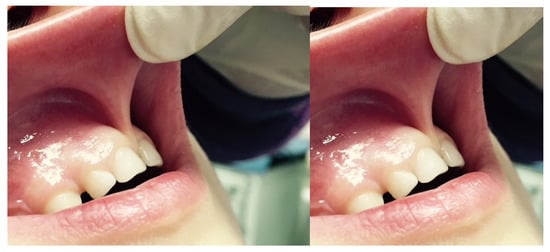

Others experience the taut, fibrous, papillary, or transpapillary insertion interincisional frenulum more frequently, which has a broad triangular upper insertion known as the tecto-labial frenulum. This kind of frenulum is regarded as a genuine dysontogenic manifestation of fetal frenulum persistence after birth [5]. The surgical approaches that are currently in use are: (a) frenectomy or excision, which involves complete removal of the frenulum; (b) frenulotomy, which involves partial removal of the frenulum (Figure 2); (c) apical repositioning of the frenulum [9,10,11].

Figure 2.

Frenulotomy: (A) Hypertrophic superior median frenulum with insertion on the interincisive papilla; (B) partial thickness incision disengages frenulum and muscle fibers and does not involve the periosteum; and (C) suture and apical repositioning on the labial side.